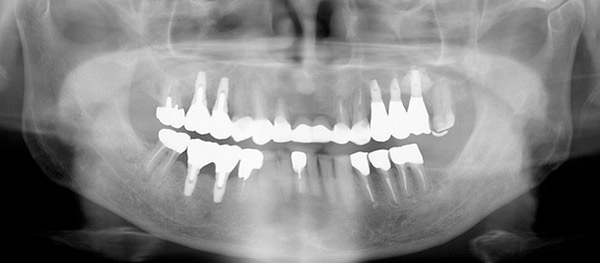

67歳男性の方です。初診時は、本人も上顎の歯すべて抜歯になり、総入れ歯を覚悟していたそうです。できる限り天然歯を温存し、治療は1年8ヶ月という長い期間かかりましたが、包括的な総合的治療により患者様に大変喜んで頂けるゴールを迎える事が出来、先日メンテナンスへ移行しました。

この患者様は、当医院まで片道1時間半もかけて来院して頂いていました。いつも明るく元気に前向きに治療を受けられていた患者様の努力が良い結果に結びついたと思います。

治療終了時